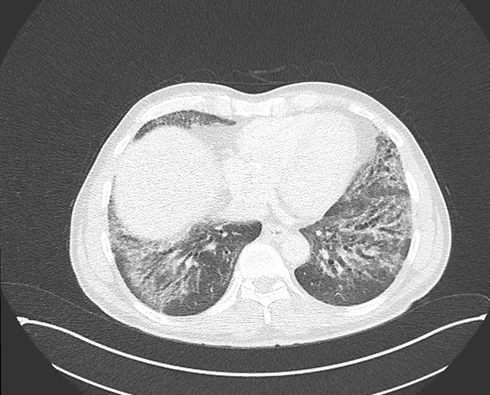

A 58-year-old with a history of nonspecific interstitial pneumonia (NSIP) pattern in high-resolution computed tomography (HRCT) (Figure 1A) presented with dyspnea and hypoxemia (SaO2 85% rest). The patient was initially followed up in another hospital; his routine serology was negative, and received treatment with mycophenolate mofetil in 2017 based on HRCT findings. Physical examination revealed bibasilar “Velcro” crackles and a V-shaped shawl erythematous rash over the chest. Pulmonary function testing demonstrated a significant decline from 2017 to 2025 in forced vital capacity (FVC: 63%pred to 53%pred) and diffusing capacity (Dlco: 55%pred to 34%pred).

Figure 1A: CT SCAN (2017): NSIP pattern bilaterally at the lung bases depicting traction bronchiectasis, fine reticulation, ground glass opacities, with subpleural sparing.